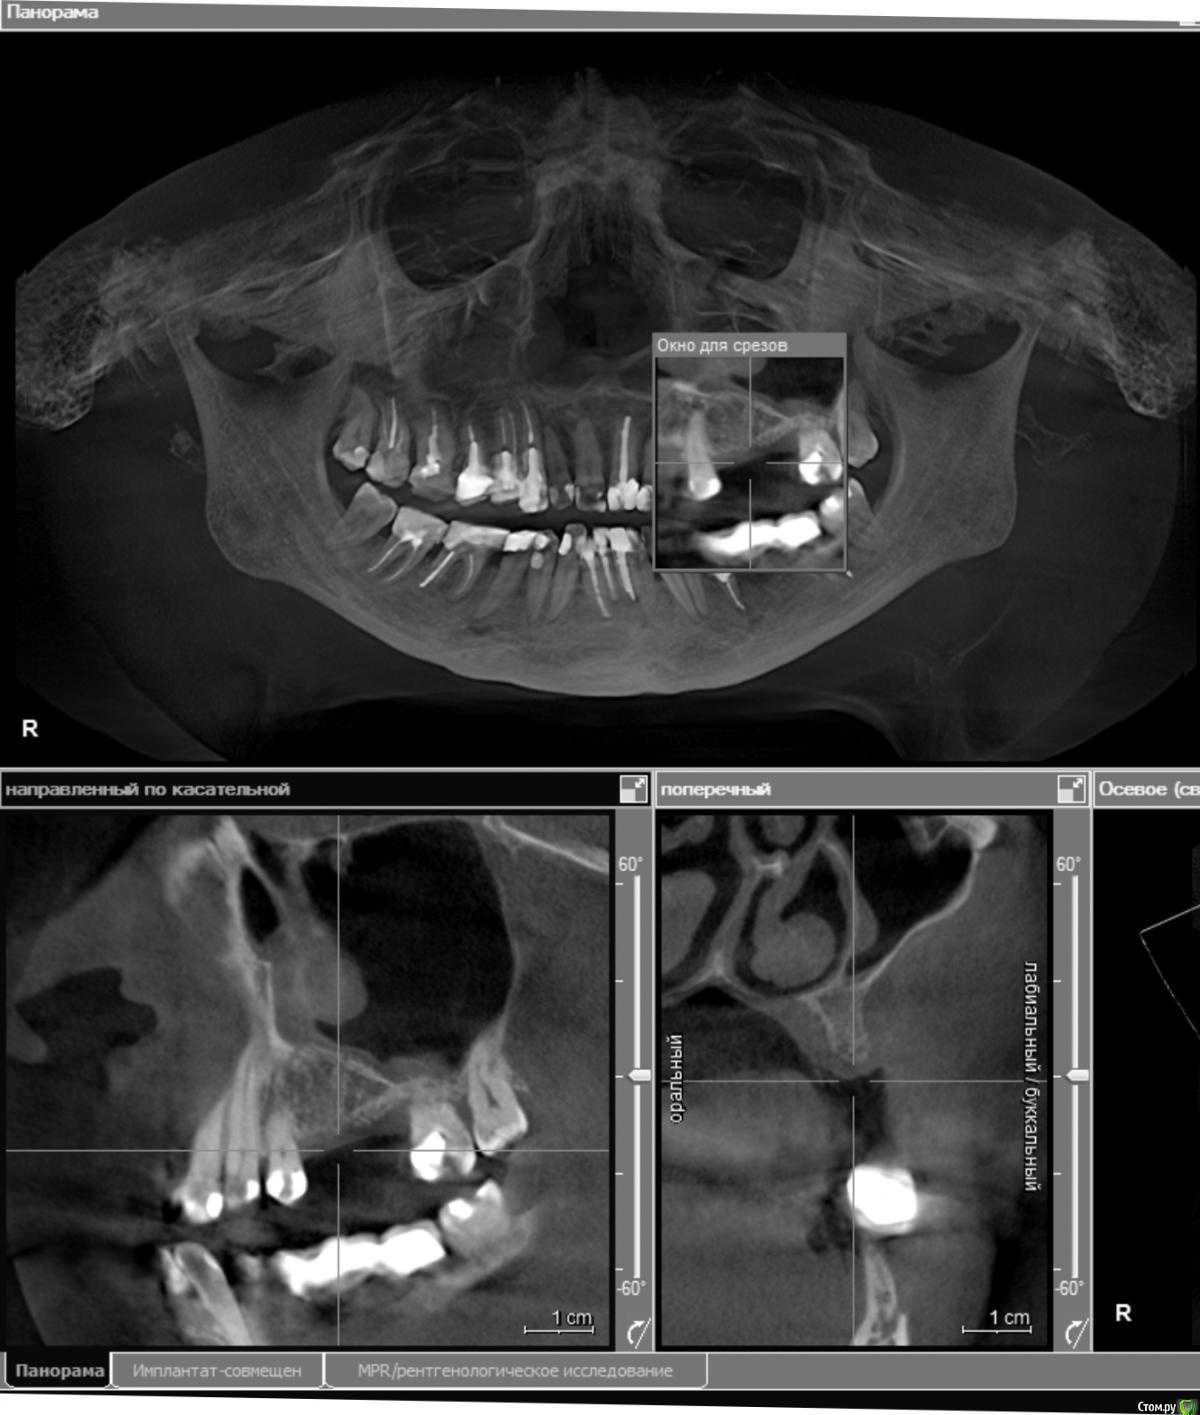

стихия Опубликовано 17 апреля, 2018 Поделиться Опубликовано 17 апреля, 2018 Здравствуйте! 8 месяцев назад были удалены верхняя левая 5-ка и 6-ка из-за кисты. Посмотрите, пожалуйста, мои снимки: возможна ли сейчас имплантация? Хватает ли там костной ткани? Проблема в том, что у меня хронический гайморит, который воспаляется каждый год, не будет ли это причиной плохой приживаемости имплантов? Можно ли при хроническом гайморите делать остеопластику? Буду очень благодарна за ответы. 2 хирурга, у которых была на очной консультации, отказались делать имплантацию в моем случае(( Ссылка на комментарий

колесников Опубликовано 17 апреля, 2018 Поделиться Опубликовано 17 апреля, 2018 (изменено) Дефект гребня в области 27 го зуба будет причиной периимплантного кармана у импланта 26. Я вижу тут 2 варианта: или Имплант Штрауман ТЛ в области 26го с синуслифтингом,+25,либо удаление 27го и мост на имплантах 25-27 Изменено 17 апреля, 2018 пользователем колесников Ссылка на комментарий

Irouil Опубликовано 17 апреля, 2018 Поделиться Опубликовано 17 апреля, 2018 Со стороны пазухи нерешаемых проблем не вижу Ссылка на комментарий